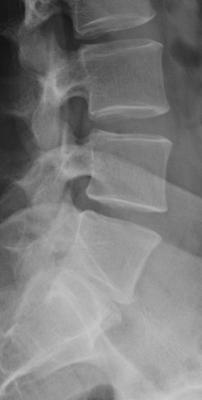

- forum_photo.jpg (8.93 KiB) 9847 mal betrachtet

Die zweite Aufnahme ist wohl eine seitliche Aufnahme, leider in einem sehr begrenzten Bereich, und zeigt eine Hyperkyphose (Rundrücken).

Die Zweite Aufahme ist eine Teilaufnahme der Lendenwirbelasaule und sagt daher nichts ueber den Gradzahl der Brustwirbelsaeule aus.